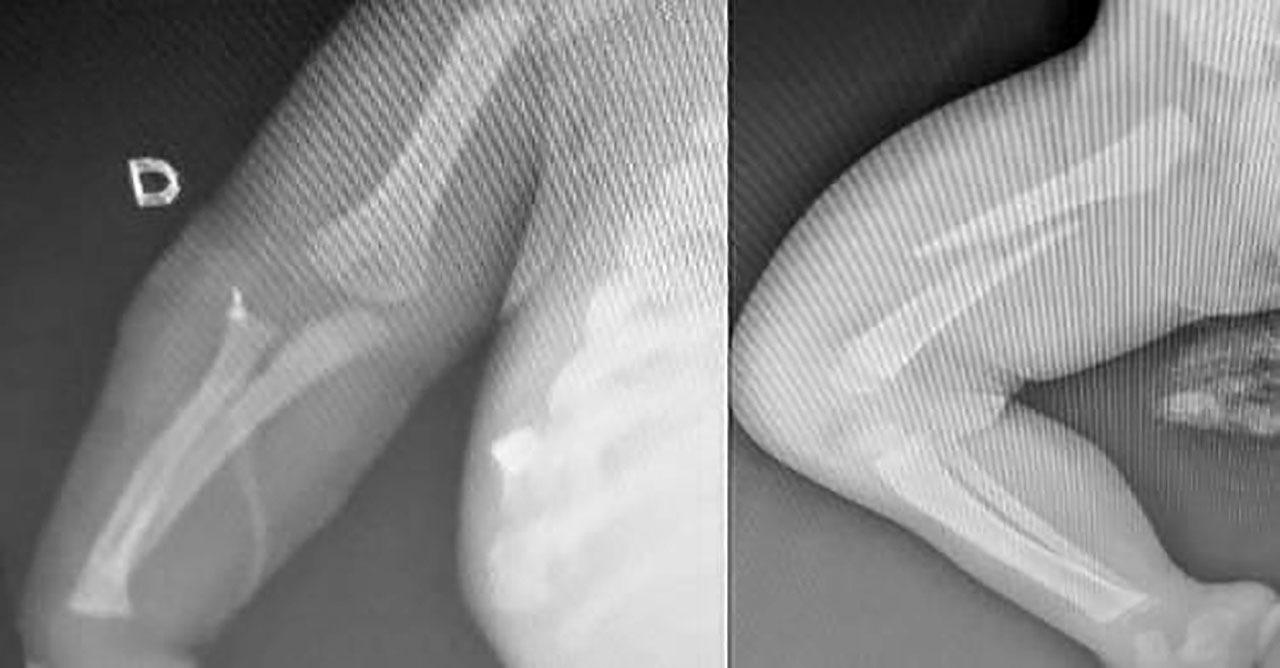

Exames médicos revelaram que a criança sofreu múltiplas fraturas, incluindo no fêmur, costelas e braço, além de uma perfuração no pulmão e diversas marcas de agressão pelo corpo. O bebê foi encaminhado para a Unidade de Terapia Intensiva (UTI) e passará por cirurgias para tratar os ferimentos.